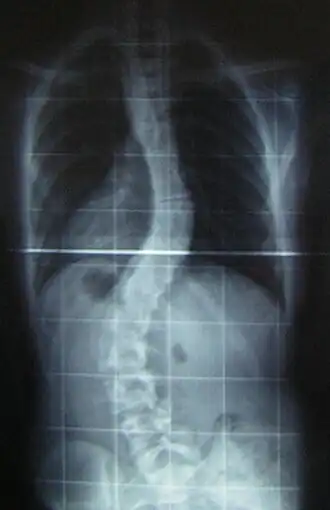

![]() Рентгеновский снимок позвоночника пациента со сколиозом с левосторонним искривлением в поясничном отделе и правосторонним искривлением в грудном отделе позвоночника. | |

Сколио́з (лат. scoliōsis ← греч. σκολιός «кривой») — трёхплоскостная деформация позвоночника у человека. Искривление может быть врождённым, посттравматическим и идиопатическим (т.е. "неизвестнопричинным").

Величина искривления позвоночника измеряется с помощью рентгеновского снимка всего позвоночника стоя. Возможны и врождённые рёберные деформации и деформации тел позвонков. С помощью этой информации можно отличить идиопатический и врождённый сколиоз. На рентгеновском снимке в боковой проекции можно также определить, есть ли врождённые деформации в этой плоскости или нарушения нормальных изгибов позвоночника — физиологических кифозов и лордозов.